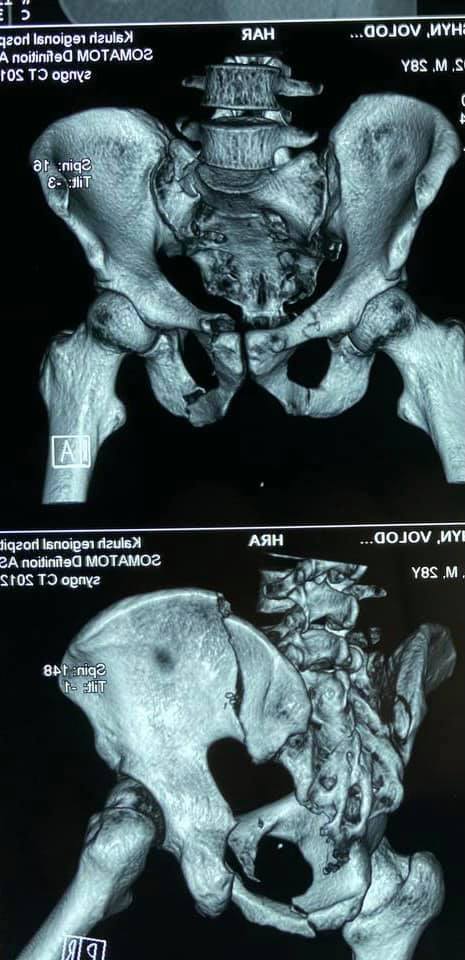

Хлопця доставила бригада швидкої медичної допомоги з Калуської райлікарні з переломом клубової кістки справа зі зміщенням, переломом бокових мас крижової кістки зліва, переломом обох лобкових та обох сідничних кісток, інформують "Вікна".

28-річний калушанин отримав травму чотирма днями раніше, 25 грудня, під час бокового стиснення деревом "кругляком" при розвантаженні лісовоза.

11 січня пацієнту було проведене оперативне втручання із залученням спеціаліста міжнародного класу. В умовах стаціонару травматологічного відділення виконано остеосинтез клубової кістки пластиною і канюльованим гвинтом, бокові маси крижової кістки фіксували канюльованим гвинтом. Лобкові кістки зафіксували пластинами та неблокуючими гвинтами.